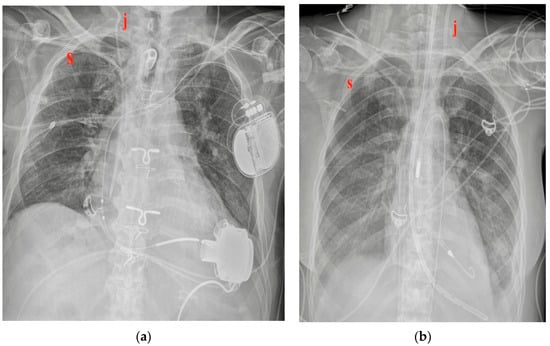

5.2. Pacemaker (PM) and Automatic Implantable Cardioverter-Defibrillator (AICD)

| PM and AICD | Leads misposition/breakage |

| Twiddler’s syndrome | |